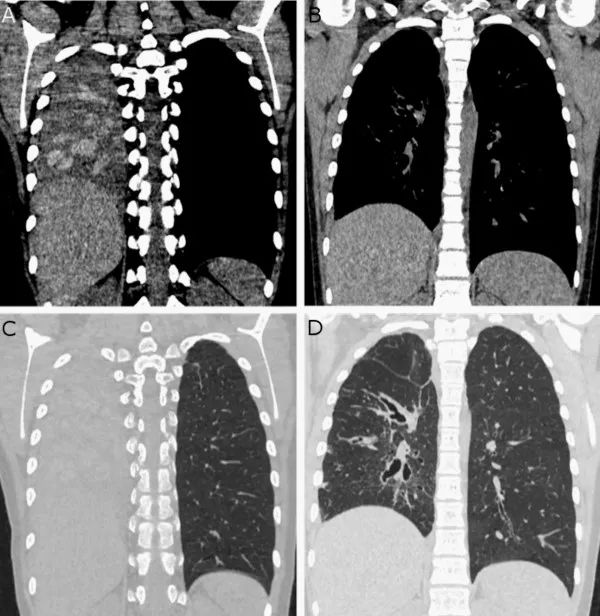

患者转诊入我科。进行一线抗生素治疗,3周后患者病情无缓解。对其进行CT检查

,图A和B为纵隔(A,B)和实质(C,D)胸部CT重建图像。图A和C显示整个右肺塌陷和实变。图A显示肺萎陷/实变内的气道树扩张,并充满比邻近肺实质更高衰减的区域。患者最终确诊为变应性支气管肺曲霉病

(allergic bronchopulmonary aspergillosis,ABPA)。ABPA需糖皮质激素

治疗,图B和图D为口服糖皮质激素治疗3个月后的图像,显示治疗后高密度粘液栓清除。同时对肺萎陷进行了治疗恢复到正常充气的肺。

曲霉阳性等。尤其CT中显示高密度粘液栓(70~150亨斯菲尔德单位)是ABPA的一个高度特异性影像特征,本例患者CT影像也显示此特征。